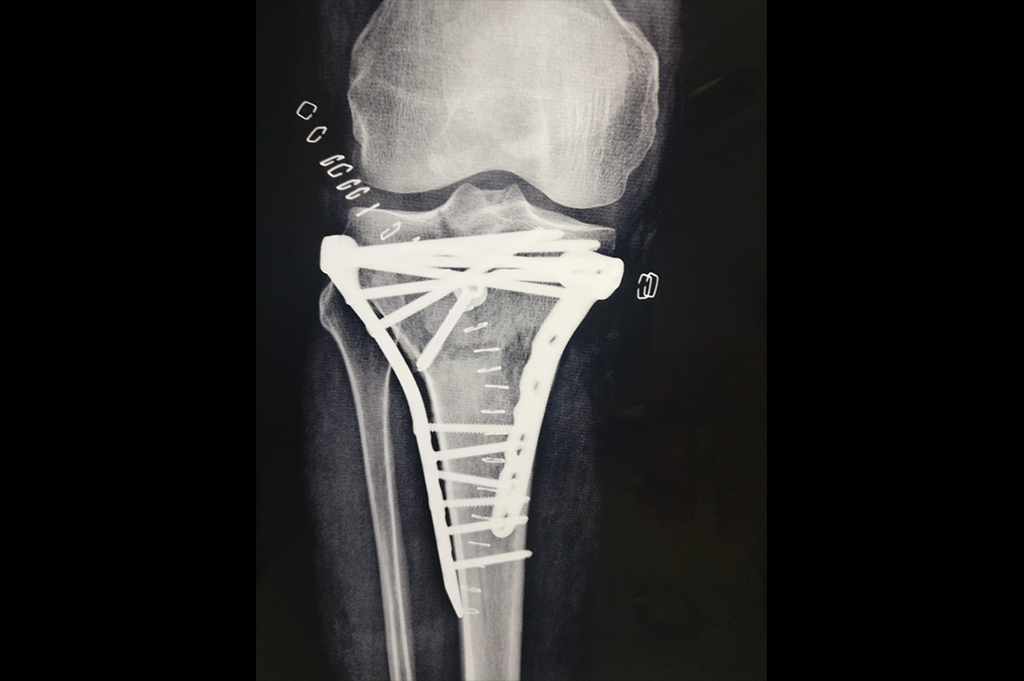

Osteoarthritis – High Tibial Osteotomy - HTO